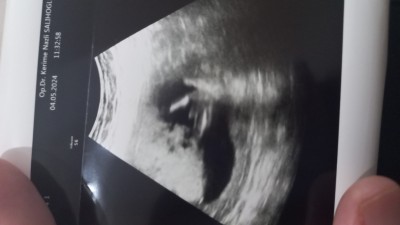

Kızlar yanlış anlamayın . Evladın kızı erkeği olmaz ama insan her iki meyveden de tatmak istiyor. Benim 3 kızım var . 4. Ye hamileyim  doktor cok net erkek dedi kesin dedi hatta oranın resmini de verdi ama cıkarken de yine de alışverişe baslamayın dedi . Kafam karıştı sizce de net degil mi neden öyle dedi acaba

image

Bacak arasi pipi bar canim ben oyle gordum

Valla baya bariz gözüküyor aslında ama doktor niye öyle dedi ki acaba. Bekle canım bikac hafta daha acele etme alışveriş için. Gönlündeki hayırlısıyla olur inşallah

Bacak arası pipi var bende gördüm hadi hayırlısı:)

Erkek :) ilk haftalarda doktorlar özellikle net konuşmaz. Benm doktorum %90kiz demişti mesela 16 hastalıktı

Uç kısmı bile belli masallah sübhanallah.benm üçüncü yuvarlak topacik birsdy var erkek dedi doktorum penis gibi bu şekilde çıkıntı da görmedik halbuki.ama bacak arası dolu ise erkek diyor doktorlar kuzum sağlıkla gelsin inşallah